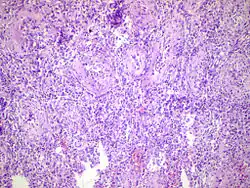

Acute epididymitis with abundant fibrinopurulent exudate in the tubules.

Histopathology image of inflamed epididymis and testis